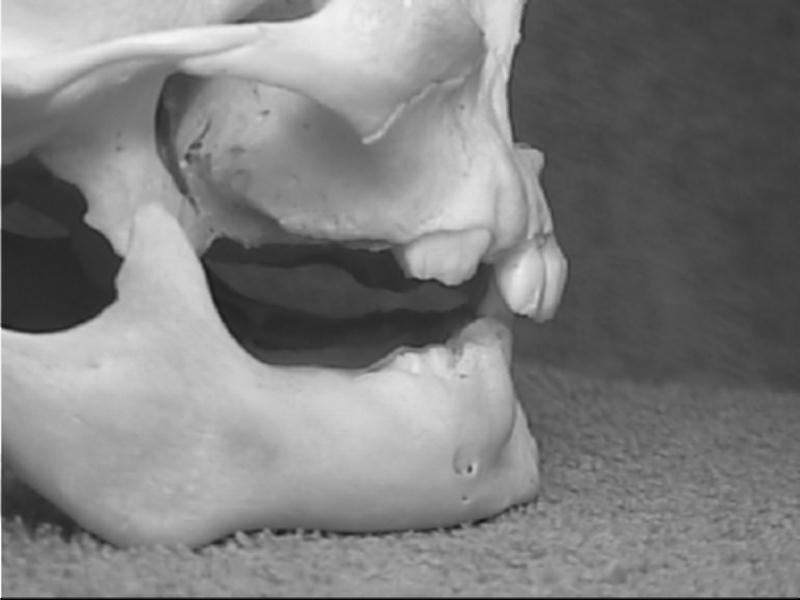

Xương sọ vùng hàm trên và dưới trẻ sơ sinh |